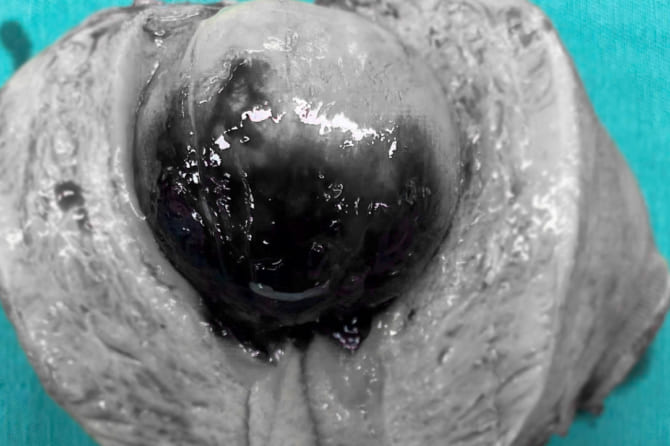

Bệnh nhân nhập viện trong tình trạng mệt mỏi, hoa mắt, chóng mặt, da xanh xao, kết quả xét nghiệm cho thấy thiếu máu nặng do rong kinh, cường kinh kéo dài. Qua thăm khám và siêu âm, các bác sĩ phát hiện khối polyp buồng tử cung lớn chiếm gần toàn bộ lòng tử cung, là nguyên nhân chính gây mất máu nghiêm trọng.

Trước diễn biến nguy hiểm, ekip bác sĩ đã nhanh chóng hội chẩn và chỉ định phẫu thuật cắt polyp buồng tử cung. Trước mổ, bệnh nhân được truyền 3 đơn vị khối hồng cầu. Nhờ kinh nghiệm chuyên môn vững vàng cùng hệ thống trang thiết bị hiện đại, ca phẫu thuật diễn ra an toàn, loại bỏ hoàn toàn khối polyp, kiểm soát tốt tình trạng xuất huyết. Sau mổ, bệnh nhân hồi phục ổn định và được xuất viện an toàn.